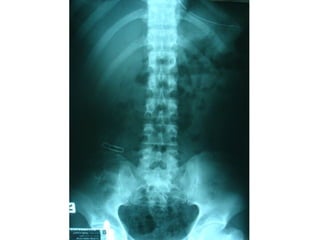

ชายไทย อายุ 38 ปี

อาชีพช่างรับเหมาก่อสร้า

ถูกยิง 3 นัดที่ท้องและขาซ

ก่อนมา รพ.ครึ่งชั่วโมง